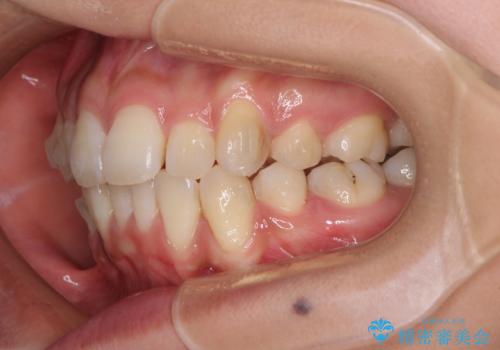

- 以前の矯正治療の後戻りにより、上下の前歯がでこぼこになってしまったことを気にして来院された患者様です。

口元がこれ以上突出することなく前歯の叢生が改善できるよう、歯と歯の間を削ってスペースを獲得し、インビザラインを用いて整えていくこととしました。

目安の装着時間である1日22時間をしっかりと実践してくださり、半年強という短期間で治療を終えることができました。